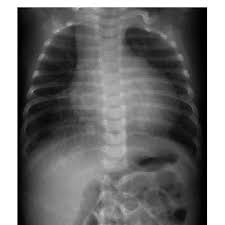

Cardiomegaly definition x ray. An enlarged heart cardiomegaly isn t a disease but rather a sign of another condition. Less severe forms of cardiomegaly are referred to as mild cardiomegaly. Maximal horizontal cardiac diameter. In equivocal cases the cardiothoracic ratio ctr can be easily calculated on a pa chest x ray.

Cardiomegaly is easily visualized on chest x ray. At autopsy cardiomegaly with right atrial and ventricular dilation was identified. Therefore medications are prescribed to such affected individuals and they may have to take them for the rest of their lives. A useful measurement on x ray is the cardio thoracic ratio which is the transverse diameter of the heart compared with that of the thoracic cage these diameters are taken from pa chest x rays using the widest point of the chest.

Maximal horizontal thoracic diameter inner edge of ribs edge of pleura figure 2. X ray presentation of cardiomegaly most people are able to recover normal heart functions but only if the condition is detected early after which it is not possible to repair the damage. An x ray of the chest helps one to detect any kind of enlargement of the heart. Other findings on chest x ray can help to determine the specific chamber that is contributing most to the enlargement of the heart.

Cardiomegaly is an enlarged heart. In most cases merely eye balling a chest x ray will be sufficient in detecting cardiomegaly as the heart is either clearly normal in size or clearly abnormally enlarged. Other tests are then needed to diagnose the condition that s causing the heart to be enlarged.